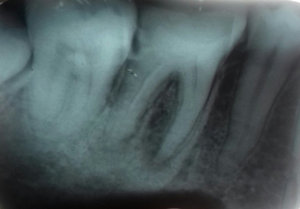

Здравствуйте. От 6-го нижнего зуба остался один корень. Зуб не болит, нервы удалены, каналы запломбированы. Зуб нужно удалить. Насколько сложна данная процедура и будут ли мне резать десну? Спасибо.

Добрый день! Если разрушение зуба не ниже основания десны и при этом каналы хорошо (!!!) пролечены (нет воспалительных процессов, грануляций), и ткани зуба плотные, то зуб можно восстановить культевой восстановительной вкладкой, а затем коронкой. Я вам рекомендую обратиться на прием к грамотному ортопеду для анализа состояния корня зуба. Если потребуется моя помощь , обращайтесь всегда рад вам помочь.